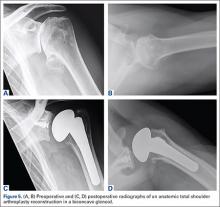

As with any TSA, the primary goals in treating patients with B2 glenoid defects are to provide the patient with a pain-free, stable, and functional shoulder (Figures 5A-5D). There are, however, a few challenges that are unique to TSA in the setting of B2 glenoid defects. Because the humeral head is often subluxated posteriorly into the defect, the anterior capsule and rotator cuff can tighten while the posterior aspect of the joint becomes lax. These soft tissues must be balanced during TSA in order to stabilize the shoulder and restore the appropriate length-tension relationship of the rotator cuff. The other primary concern is restoration of appropriate glenoid version and lateralization. To accomplish this, the most common techniques utilized are asymmetric reaming, bone graft augmentation, and glenoid component augmentation.27,28